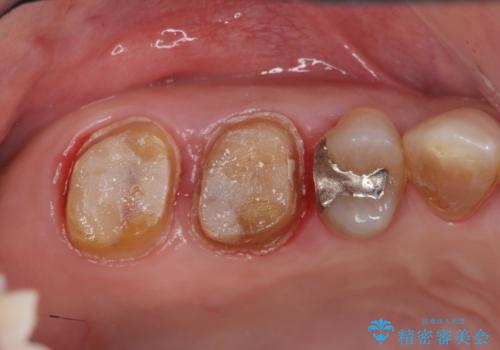

歯周ポケットの除去と再補綴治療

歯周組織検査・X線検査の結果、中等度の歯周病であることがわかりました。

歯周ポケットの除去を歯周外科により行ったのち精度が高く清掃のしやすいセラミック治療による再補綴を行います。